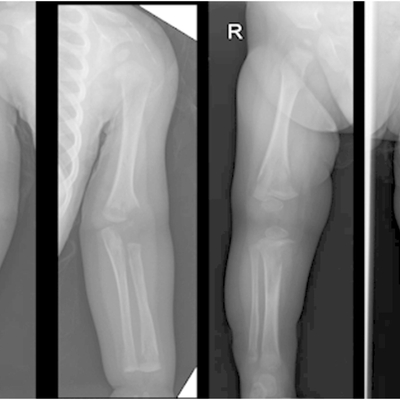

Click on an image below to view more info.